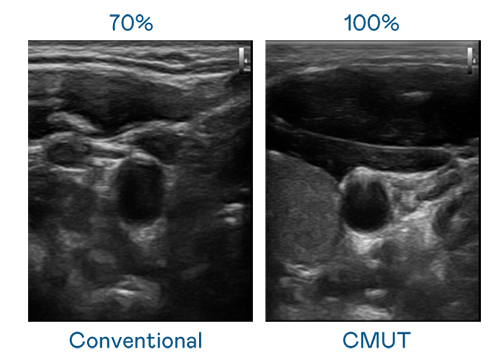

CMUT 技术是一种用电容式微机电元件来产生超音波讯号的技术。与传统 PZT 压电式技术相比,CMUT 频宽增加 30%,更宽频的超音波讯号让影像解析度大幅提升,是实现高影像品质医疗超音波扫描、促进精准医疗发展的关键技术。

大频宽带来超清晰影像

超音波影像的解析度高低,首先取决于探头能发出的讯号频宽。利来国际真人娱乐 CMUT 可提供高清晰的超音波讯号,提供高频宽、高灵敏度、影像纹理细节更高的超音波影像,协助医护人员缩短影像判读时间及利用精准的医疗影像进行诊断。